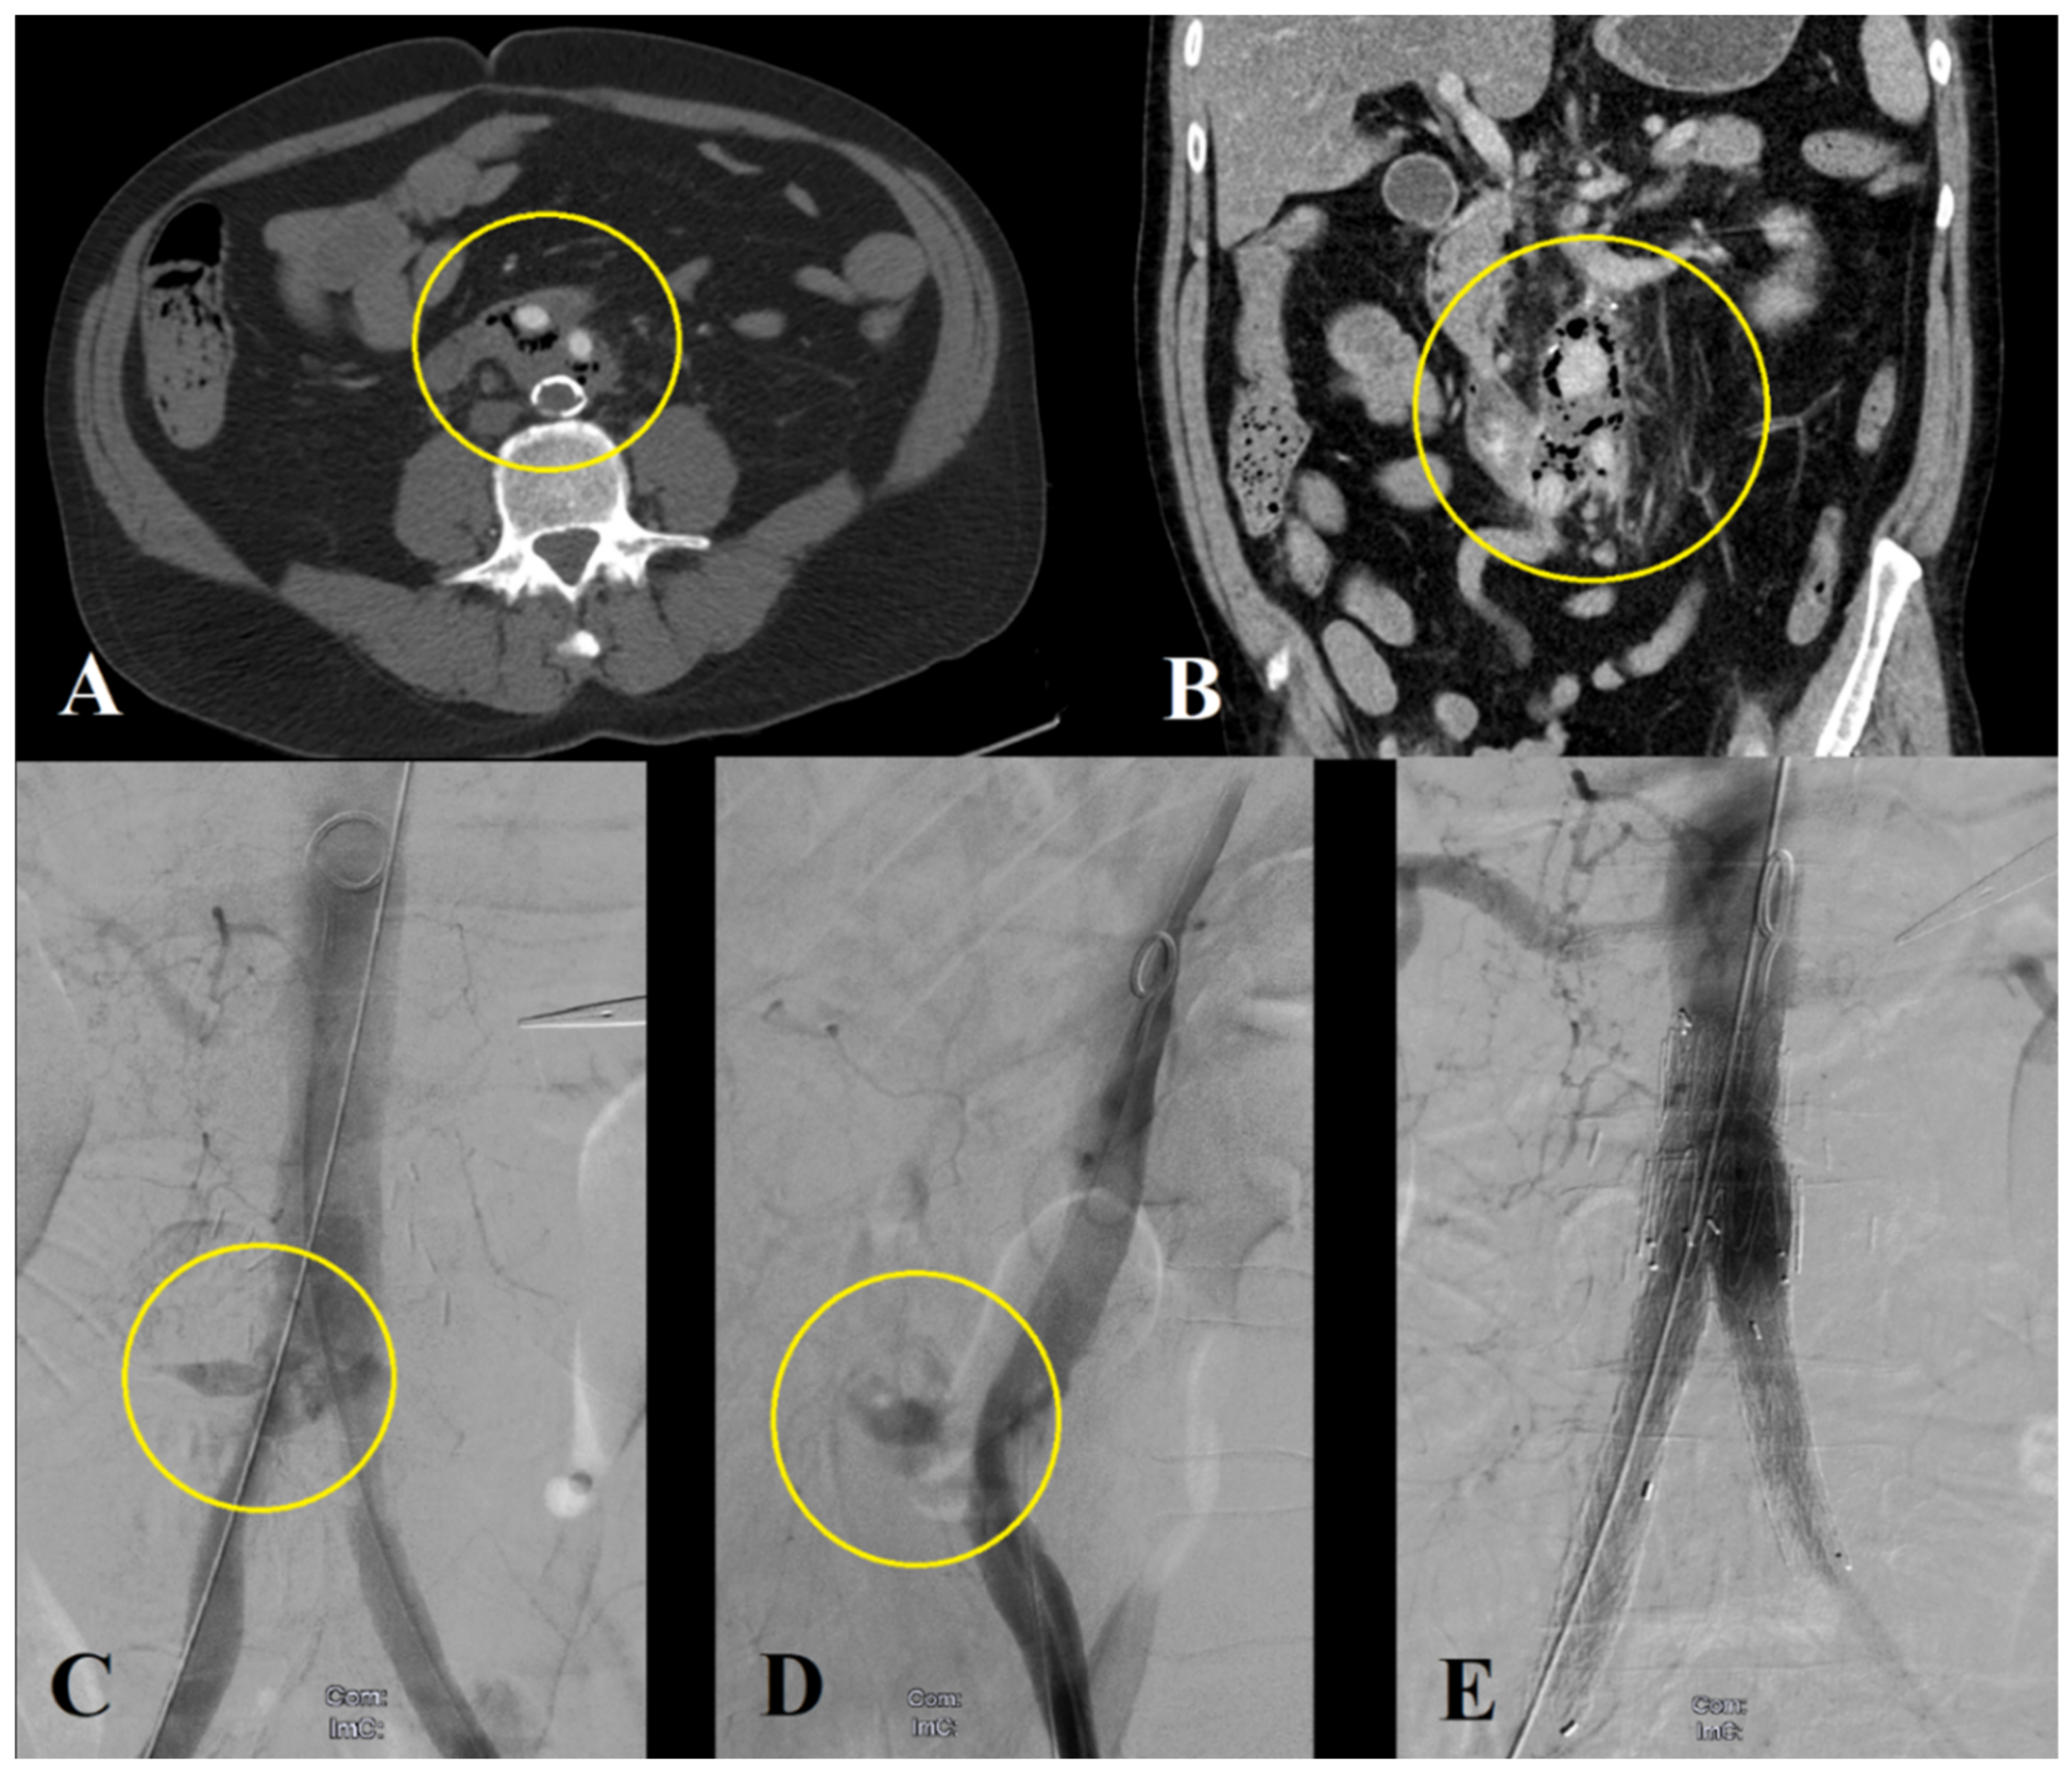

3.2.2. Endovascular Repair

3.2.3. Hybrid Repair